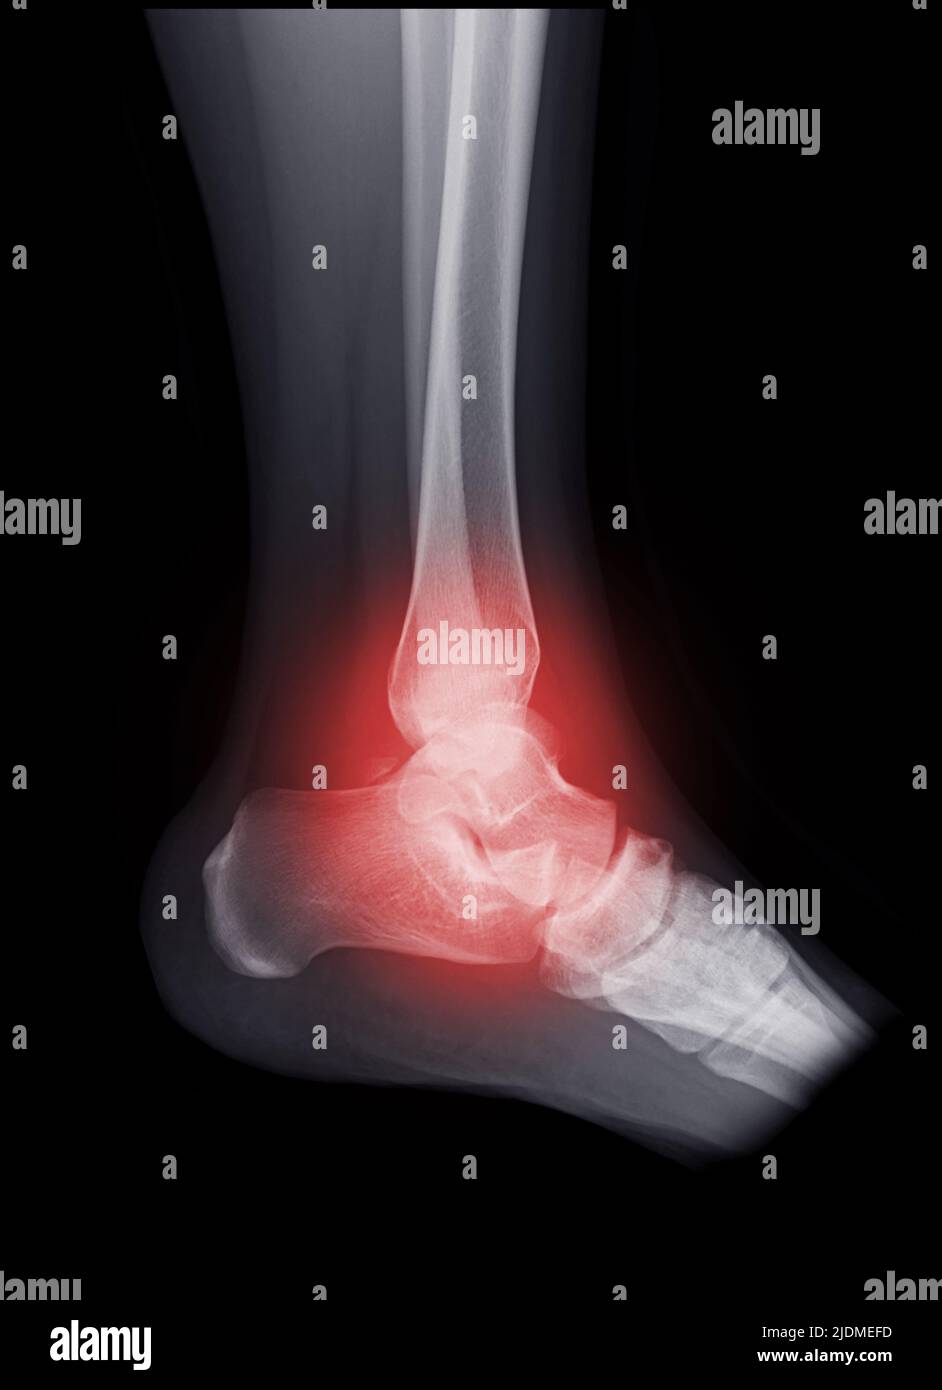

From stock.adobe.com

Xray ankle joint or Radiographic image or xray image of right ankle joint for diagnostic bone Ankle Bone Fracture X Ray They can show where the bones are broken and if any of the bones. Ankle fractures are usually bony injuries involving the distal tibia (medial malleolus) or distal fibula (lateral malleolus). A broken ankle, or ankle fracture, is one of the most common causes of ankle pain. An ankle fracture happens when you break one or. Ankle fractures account for. Ankle Bone Fracture X Ray.